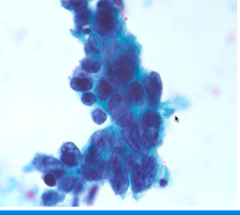

malignant cells showing pleiomorphic, anisocytosic, and discohesive feature

Back